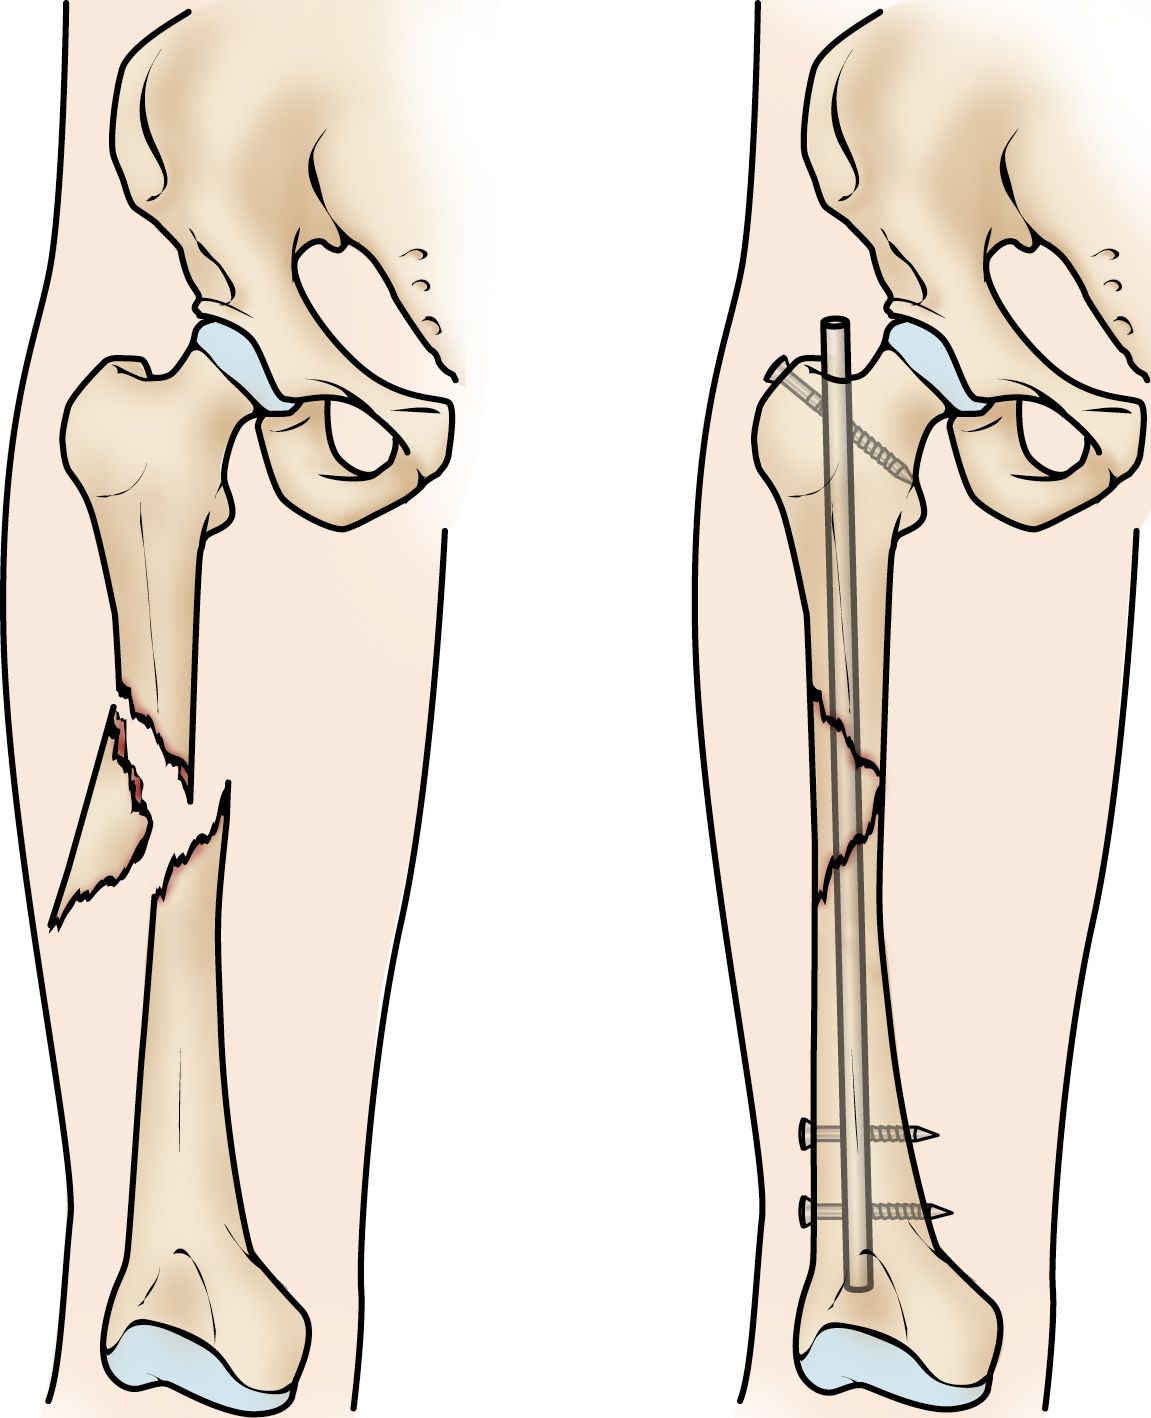

Clavos intramedulares. Actualmente, la utilización de clavos intramedulares es el método que la mayoría de los cirujanos usan para tratar fracturas de la diáfisis femoral. Durante el procedimiento, se introduce una barra metálica especialmente diseñada en el canal del fémur. Esta barra atraviesa la fractura para que se mantenga en su posición.

Los clavos intramedulares ofrecen una fijación fuerte, estable y de extensión total.

Puede introducirse un clavo intramedular en el canal de la cadera o la rodilla. Los tornillos se colocan por encima y por debajo de la fractura para mantener la pierna alineada correctamente mientras el hueso se repara.

Los clavos intramedulares suelen estar fabricados con titanio. Vienen en varios tamaños y diámetros para adaptarse a la mayoría de los fémures.